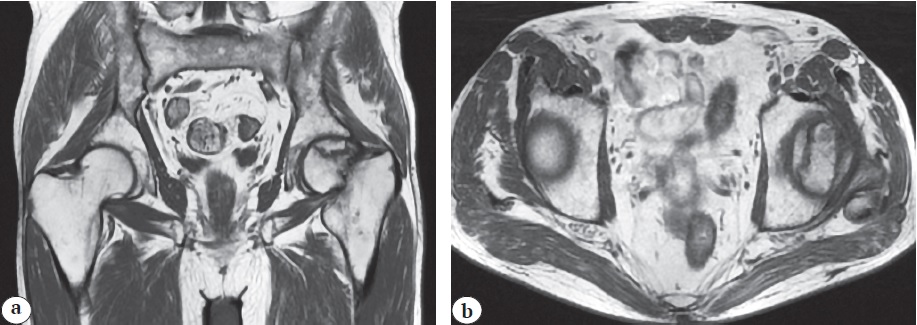

On admission, the local status revealed a pain syndrome (6 points according the VAS) aggravated by active and passive movements. The patient used a crutch for walking and exhibited significant limping. There was a relative shortening of the left lower limb by 2 cm. No redness or swelling was observed in the left hip joint area, and local temperature was not elevated. Thigh muscle atrophy was present, measuring 3 cm compared to the contralateral side. The patient reported temporary relief from non-steroidal anti-inflammatory drugs. X-rays, CT, and MRI showed signs of stage 3B (late) aseptic necrosis of the left femoral head according to the ARCO classification (Fig. 1, 2).

Fig. 2. Clinical case 1. MRI in frontal (a) and axial (b) projections: osteonecrosis of the left femoral head — stage 3B (late) according to the ARCO classification